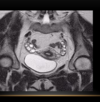

Imaging modality and what is seen in the ovaries

T2 weighted MRI (fat & water are white)

Ovaries containing follicular cysts